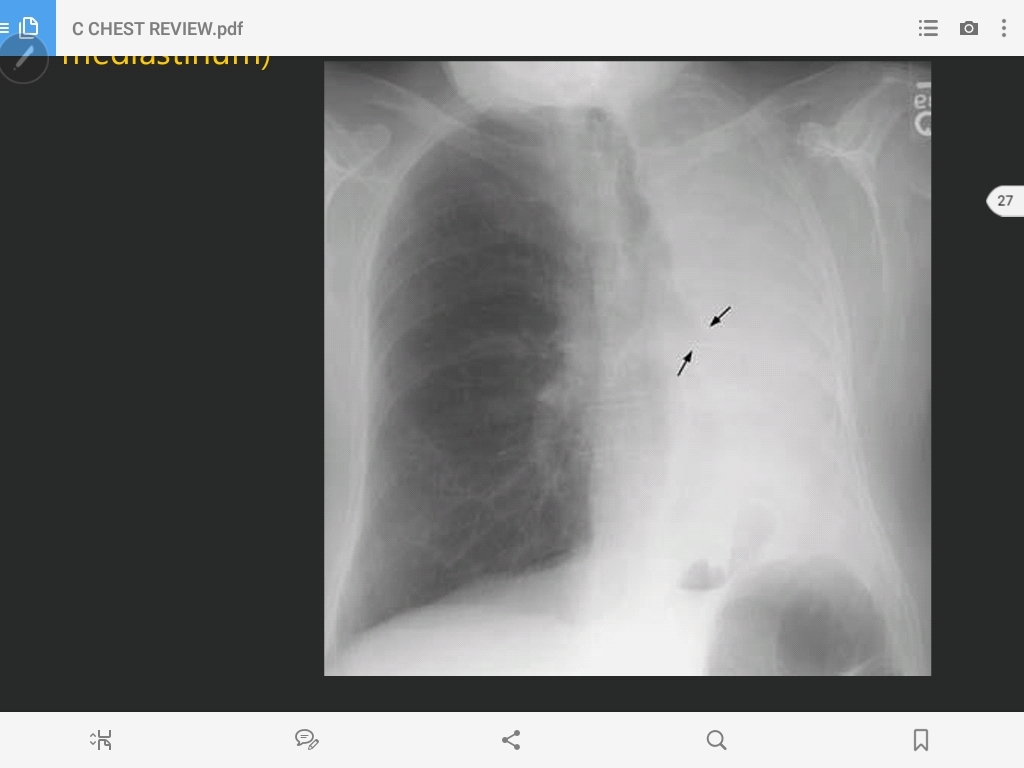

enlarged hilum (bronchogenic carincoma

enlarged hilum (bronchogenic carincoma)